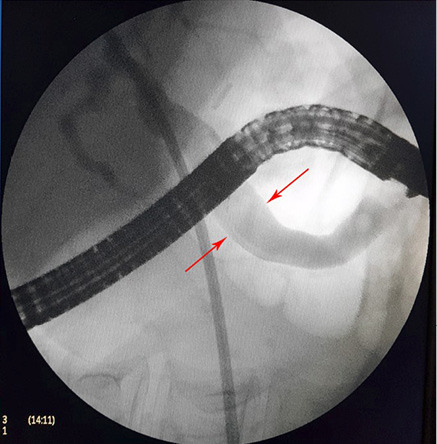

4 pav. ERC vaizdas: askaridės šešėlis BTL (pažymėta rodyklėmis)

5 pav. ERC vaizdas: BTL šešėlis pašalinus askaridę (pažymėta rodyklėmis)

Pacientei įtarta pilvo skausmų priežastis – tulžies latakų akmenligė, nesant mechaninės geltos. Priimtas sprendimas atlikti duodenoskopiją ir ERC tyrimą. Duodenoskopijos metu įvertinta, kad papilla Vateri yra po PST procedūros. Kontrastavus BTL, pastebėtas >5 cm ilgio 4 mm skersmens prisipildymo defektas lygiais kontūrais. Naudojant Dormia krepšelį, iš tulžies latako pašalintas prisipildymo defektas – askaridė (3–5 pav.). Atlikus procedūrą, pacientės sveikatos būklė pagerėjo, pilvo skausmas regresavo, nesikartojo. Papildomai atlikta dehelmintizacija mebendazolu, antihelmintiniu vaistiniu preparatu („Vermox“).

Sergant tulžies latakų askaridoze, kraujo tyrimai gali atitikti normos ribas. Tokiu atveju įtarti patologiją padeda paciento nusiskundimai, išsami ligos ir gyvenimo anamnezė (kelionės, namų aplinka, valgymo įpročiai ir sąlytis su dirvožemiu). Specifinių (ligą diagnozuojančių) laboratorinių tyrimų askaridozei nustatyti nėra. Tiksliai diagnozuoti parazitų invaziją į žarnyną, kai laboratoriniai tyrimai nepatologiniai, galima identifikavus askaridžių kiaušinėlius paciento išmatose [3, 27]. Kirmėlių migraciją į tulžies latakus galima nustatyti atlikus ultragarsinį tyrimą. Dažnai ultragarsu pastebimas prisipildymo defektas BTL. Jis būna pailgos arba cirkuliarios formos, be tulžies latakų akmenims būdingo šešėlio – artefakto. Dėl šios priežasties ultragarsu stebimas prisipildymo defektas dar vadinamas „minkštu“ radiniu (1, 2 pav.). Nors ultragarsinis tyrimas vertinamas kaip jautrus ir specifiškas (atitinkamai 40–70 proc. ir 90 proc.), tyrimo kokybė priklauso ir nuo tyrėjo patirties. Tulžies latakuose esant oro po buvusių intervencijų arba kirmėlių maceracijos metu, kai kirmėlė negyva, ji gali būti nepastebėta [2, 3].